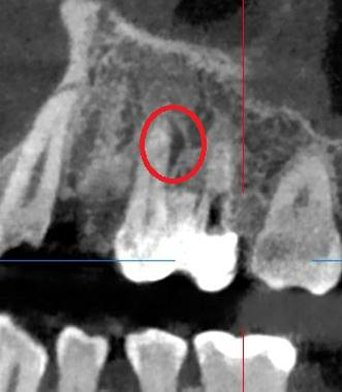

Проблема: У пациента жалобы на боли при накусывании и дискомфорт во время жевания. Ранее обращался в другие клиники, где было рекомендовано удаление зуба ввиду невозможности его перелечивания.

Лечение: Проведено перелечивание корневых каналов под микроскопом с удалением ранее внесённых материалов, тщательной механической и медикаментозной обработкой каналов и их последующей герметичной обтурацией. После лечения каналов выполнено восстановление коронковой части зуба.